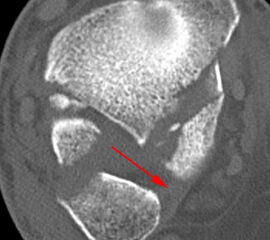

Liegt eine Fraktur des oberen Sprunggelenks vor, ist sowohl zur Entscheidung für ein konservatives oder operatives Vorgehen, als auch zur Operationsplanung, ein ausreichendes Verständnis der Fraktur und ihrer Morphologie notwendig. Insbesondere bei komplexen Verletzungen ist dafür die konventionelle Röntgenaufnahme in vielen Fällen nicht ausreichend. So konnten z.B. Black et al. zeigen, dass die operative Strategie zur Versorgung von OSG-Frakturen in 24% basierend auf einer zusätzlichen CT-Bildgebung relevant geändert wurden 7. Dies betraf die Lagerung, die Wahl des Zuganges und die Art der osteosynthetischen Versorgung. Besonders häufig änderte sich das Vorgehen bei Verletzungen des medialen (21%) und des posterioren Malleolus (15%). Darüber hinaus führten dislozierte (dislozierte Frakturen 31% vs. nicht-dislozierte Frakturen 20%) oder komplexe Frakturen (Trimalleolar-Frakturen 29% vs. Unimalleolar-Frakturen 10%) besonders häufig zu relevanten Änderungen des operativen Vorgehens. Die Computertomographie ist daher, insbesondere bei Bi- und Trimalleolar-Frakturen, essentiell für das Verständnis der Fraktur und somit für die Planung und Durchführung der Operation. In Abbildung 4 und 5 sind exemplarisch ein Röntgen- und ein CT Befund gegenübergestellt.